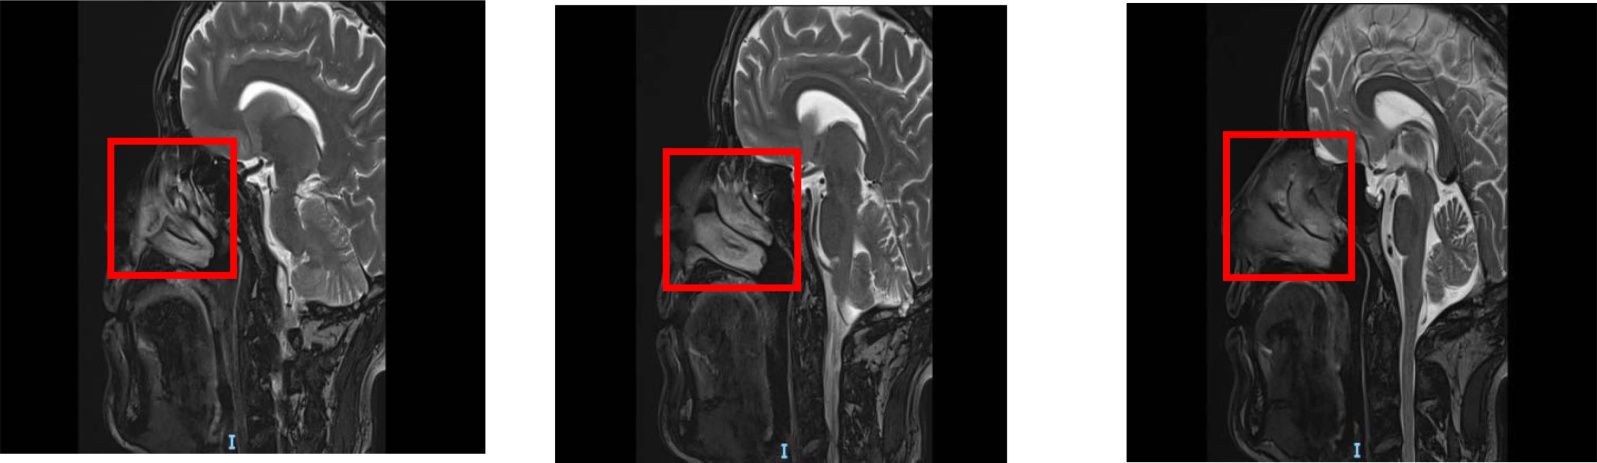

例1:患者男,22岁。因“鼻塞1年余,反复左侧鼻腔出血1个月”于2021年3月11日入院,伴嗅觉减退、头痛,无流涕,无体重减轻,无其他病史。查体:左侧鼻腔见新生物堵塞。鼻窦计算机断层扫描(Computed Tomography, CT):左侧鼻腔、鼻咽腔及左侧副鼻窦内软组织密度影,考虑鼻息肉;全组副鼻窦炎(见图1)。入院后反复发热,体温最高达38.5℃,伴咳嗽、咳痰,血常规示白细胞、中性粒细胞计数、C反应蛋白均升高,予以“头孢呋辛(1.5 g q8h)”静脉滴注,症状控制欠佳,后将抗生素升级为“头孢他啶(2.0 g q8h)”并采取止咳、降温等治疗,1周后病情稳定,遂行鼻内镜下鼻窦开放术 + 鼻腔鼻窦肿物切除术。术中发现该肿物触之易出血,完整切除后,依次开放左侧上颌窦、筛窦、额窦和蝶窦,发现新生物起源于上颌窦,上颌窦内侧壁明显硬化。术中出血量较大,约400 ml,术后血常规示红细胞、血红蛋白下降,其他实验室指标基本正常,考虑术中一过性出血,故未予以输血,仅积极补液。术后常规病理:(左侧鼻腔鼻窦)小圆细胞肿瘤,结合免疫组化考虑为骨外尤文肉瘤。免疫组化:肿瘤细胞CD99(+),F1i-1(+/-),NKX2.2(+),β-catenin浆(+),Ki-67(+, 30%~40%),Vimentin(+/-),CD56灶性(+),Syn灶性(+),CK(-),Desmin(-),LCA(-),CD3(-),CD20(-),CD21(-),MyoD1(-),INI-1无缺失,SMA(-),Pax-5(-),Myogenin(-),CD79a (-) (见图2)。故诊断为鼻腔鼻窦小圆细胞肿瘤(骨外尤文肉瘤T4N0M0)。化疗前后,行腹部、心脏彩超,鼻咽部、颈部磁共振成像(Magnetic Resonance Imaging, MRI)、胸部CT等检查,均未见复发与转移。目前患者术后4年余,电话随访无复发及转移。

Figure 1. Nasal CT scan: soft tissue density shadows in the left nasal cavity, nasopharynx and left paranasal sinuses, suggestive of nasal polyps with pansinusitis

1. 鼻部CT左侧鼻腔、鼻咽腔及左侧鼻窦,可见软组织密度影,考虑为鼻息肉